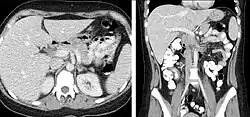

Body Imaging

A CT scan can be used for detecting both acute and chronic changes in the lung parenchyma, the tissue of the lungs.[66] It is particularly relevant here because normal two-dimensional X-rays do not show such defects. A variety of techniques are used, depending on the suspected abnormality. For evaluation of chronic interstitial processes such as emphysema, and fibrosis,[67] thin sections with high spatial frequency reconstructions are used; often scans are performed both on inspiration and expiration. This special technique is called high resolution CT that produces a sampling of the lung, and not continuous images.[68]

CT is an accurate technique for diagnosis of abdominal diseases like Crohn's disease,[69] GIT bleeding, and diagnosis and staging of cancer, as well as follow-up after cancer treatment to assess response.[70] It is commonly used to investigate acute abdominal pain.[71] Non-enhanced computed tomography is today the gold standard for diagnosing urinary stones.[72] The size, volume and density of stones can be estimated to help clinicians guide further treatment; size is especially important in predicting spontaneous passage of a stone.[73]